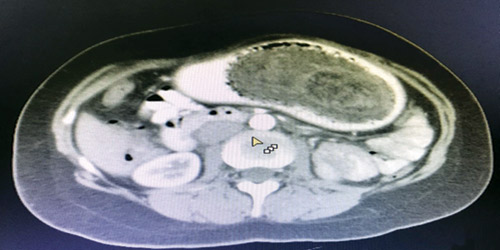

حضرت سيدة في عقدها الثالث لعيادة الجهاز الهضمى بمستشفى المواساة بالدمام تشتكى من آلام مبرحة بأعلى البطن وبالكشف الطبى وبعمل أشعة مقطعية ومنظار معدة اتضح وجود كتلة من الشعر تملأ جوف المعدة مع بداية الاثنى عشر. ووضع الفريق الطبي المكون من استشاري الجراحة العامة والمناظير، استشاري التخدير، إضافة إلى استشاري الجهاز الهضمي والمناظير الخطة العلاجية والجراحية للمريضة القيام بالإجراء الجراحي الذي تم خلاله استخراج كتلة شعر تزن 3 كيلو جرامات من معدة المريضة التي حولت بعدها للمتابعة بالقسم الداخلي لإجراء باقي الاستشارات اللازمة وتحسنت حالة المريضة التي غادرت المستشفى بصحة جيدة.